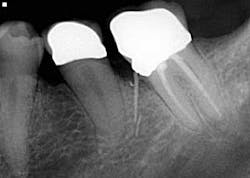

• File separation

Spin, spin, and snap! This is my least favorite endodontic complication (figure 3), which is why I wrote an entire article on it.